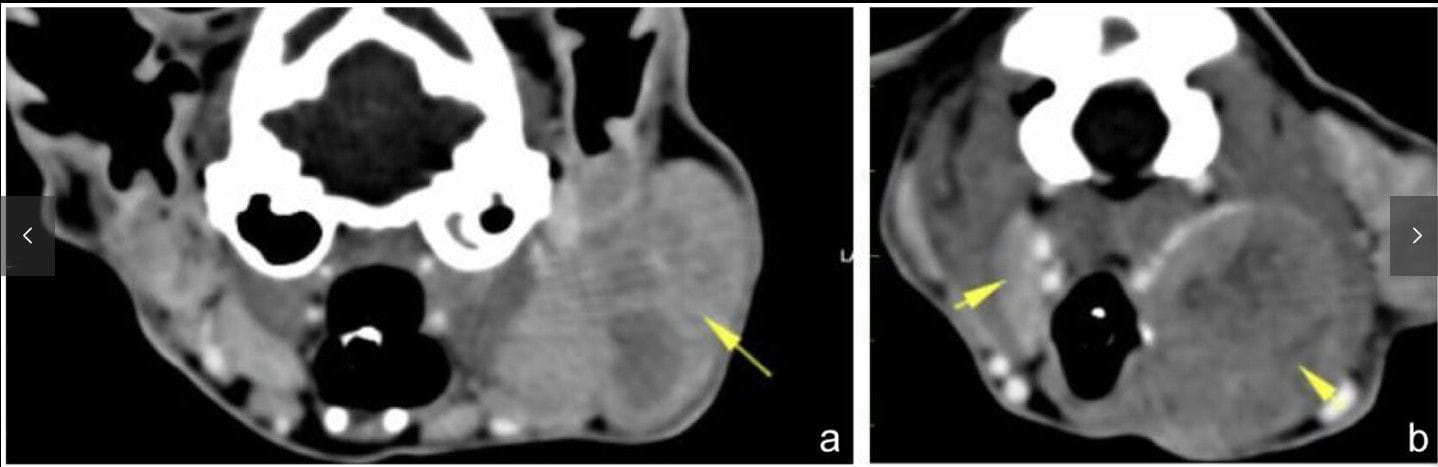

CT findings of a domestic shorthair cat aged 10 years 8 months (case 1) diagnosed with steroid-responsive neutrophilic lymphadenitis: (a) left parotid lymphadenomegaly (yellow arrow) (3.9 × 2 cm); and (b) left medial retropharyngeal lymphadenomegaly (2.5 cm) with heterogeneous contrast uptake and right medial retropharyngeal lymph node (0.5 cm thickness) (yellow arrows)